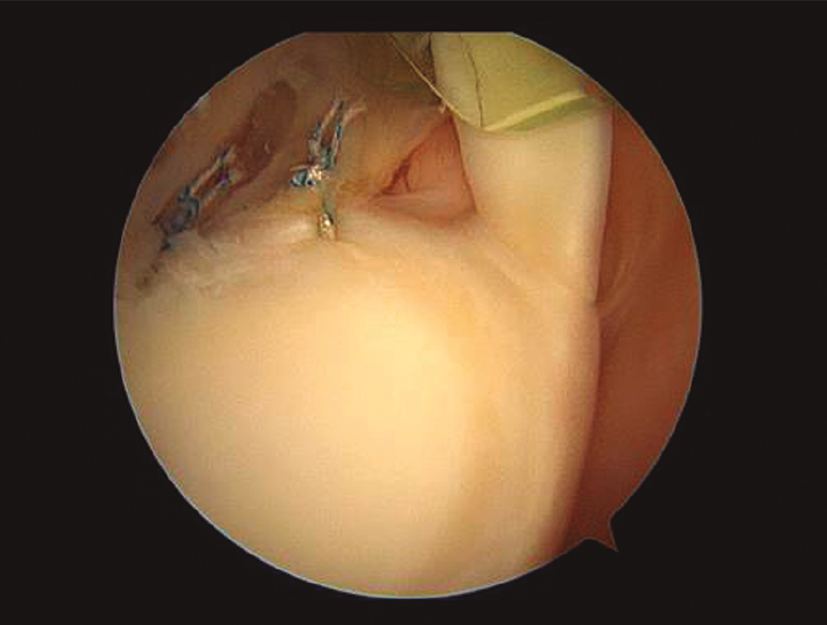

Microinestabilidad de hombro: microcapsuloplastia

Las pequeñas lesiones capsuloligamentosas y del labrum, características de los cuadros de micro­inestabilidad de hombro, requieren un tratamiento común con otras formas “mayores” de inestabilidad. En estos casos, los gestos de reconstrucción serán mucho más limitados.